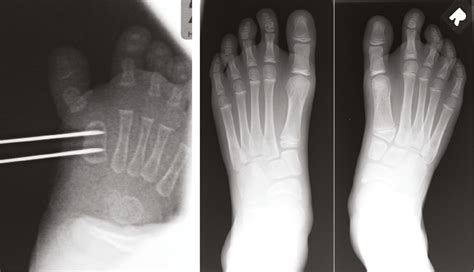

• Fractures: The epiphyseal plate is particularly vulnerable to injuries in children, as it is the weakest part of the growing bone. Fractures involving the epiphysis require careful management to ensure proper healing and to minimize the risk of growth disturbances. Pediatric nurses are involved in the initial assessment, stabilization, and ongoing care of these injuries.

• Imaging Studies: Order appropriate imaging studies, such as X-rays, to visualize the epiphysis and identify any fractures or dislocations. In some cases, advanced imaging such as MRI may be necessary to assess soft tissue injuries.

• Immobilization: Apply appropriate immobilization devices, such as splints or casts, to stabilize the injured area and promote healing. Ensure that the immobilization does not compromise neurovascular status.